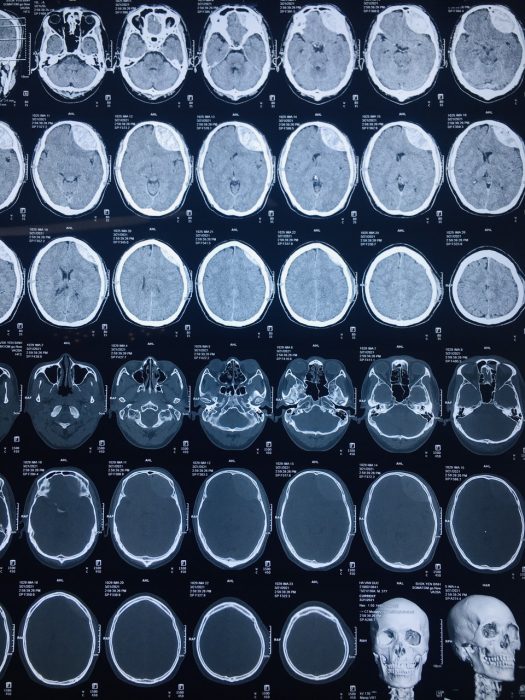

Các bác sỹ tiến hành cấp cứu hồi sức và thăm khám, chụp CT sọ não phát hiện tổn thương sọ não là khối tụ máu ngoài màng cứng bên trái, vỡ lún xương thái dương bên trái. Chỉ định phẫu thuật cấp cứu lấy máu tụ ngoài màng cứng.

Hình ảnh chụp CT scan của Bệnh nhân Hà.V.Đ